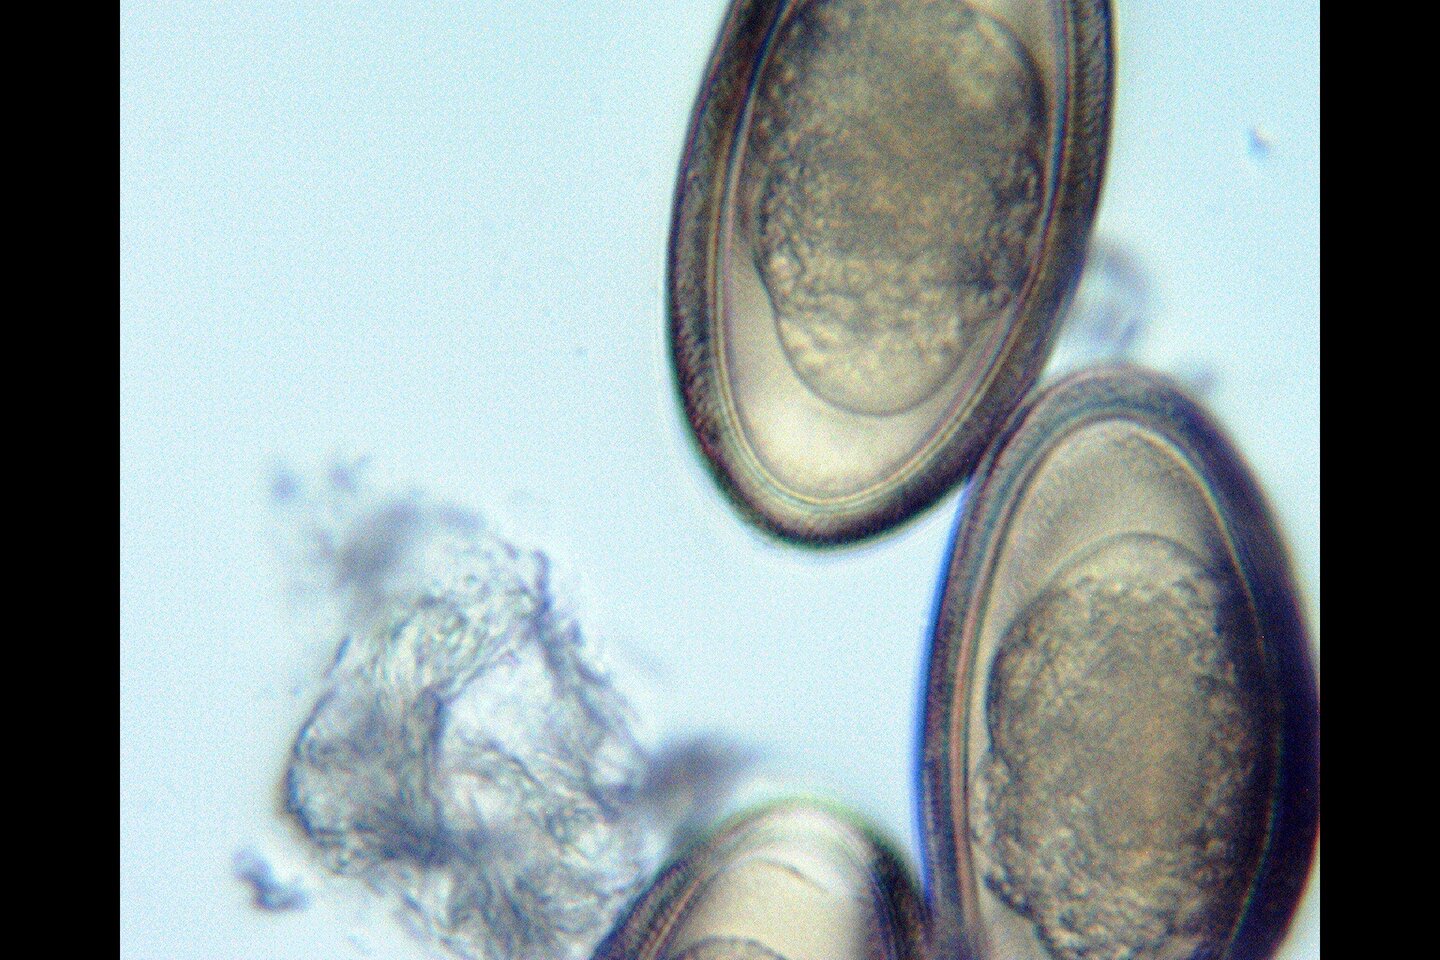

• Fecal Description - His last poo was small, but good consistency / color. Ran a fecal float myself within 24hrs (refrigerated - vet was closed). Pics below... def pinworm, plus mystery circular object. I am wondering if its plant matter... although yo umay see 2 bubbles on some, when focusing/adjusting microscope there are usually many bubbles, not just one or two. Doesn't seem to match the images I've seen of coccidia thus far, but I am not an expert. Previously clean fecal in spring.

Here are a few pics from a fecal, which shows pinworm quite clearly (counted 3... he was taking reptaid prior to seeing vet, but we stopped it once prescribed antibiotics). There is a mystery round object with bubbles... but note that it does not have only 1 or 2 bubbles, but many. Even where it may look like 1 or 2, when the microscope is adjusted you will typically see many bubbles.